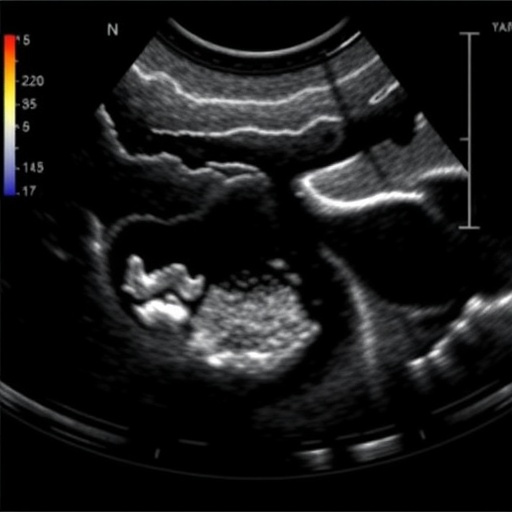

Ultrasound has long been established as a safe, non-invasive imaging modality, but its application in assessing urinary tract morphology and function in young patients, particularly those with myelomeningocele, is relatively novel. Dynamic ultrasound enables a real-time assessment of bladder and urethral function, reflecting changes as they occur. This study aims to harness the power of this technique to map out urinary tract abnormalities more effectively than traditional, static imaging methods.

Throughout the course of the study, the researchers monitored several newborns and young infants diagnosed with myelomeningocele, documenting parameters such as bladder capacity, detrusor pressure, and urinary flow rates. Preliminary findings indicated that many of the subjects exhibited significant variances in bladder function and morphology when compared to normative data. Such deviations suggest potential pathways for developing comprehensive care plans tailored to individual patients rather than relying on a one-size-fits-all approach.

Another essential aspect of the research is understanding the relationship between morphologic abnormalities and functional urinary issues. By correlating structural abnormalities seen in ultrasound images with clinical symptoms, the researchers hope to provide clearer guidelines for healthcare providers. This understanding may also extrapolate beyond just monitoring — potentially guiding surgical interventions or pharmacological therapies aimed at improving urinary tract function in this vulnerable population.